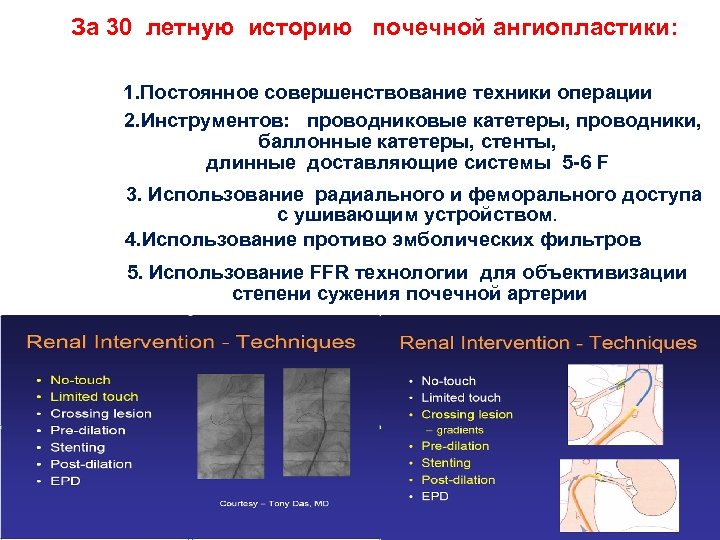

За 30 летную историю почечной ангиопластики: 1. Постоянное совершенствование техники операции 2. Инструментов: проводниковые катетеры, проводники, баллонные катетеры, стенты, длинные доставляющие системы 5 -6 F 3. Использование радиального и феморального доступа с ушивающим устройством. 4. Использование противо эмболических фильтров 5. Использование FFR технологии для объективизации степени сужения почечной артерии

За 30 летную историю почечной ангиопластики: 1. Постоянное совершенствование техники операции 2. Инструментов: проводниковые катетеры, проводники, баллонные катетеры, стенты, длинные доставляющие системы 5 -6 F 3. Использование радиального и феморального доступа с ушивающим устройством. 4. Использование противо эмболических фильтров 5. Использование FFR технологии для объективизации степени сужения почечной артерии